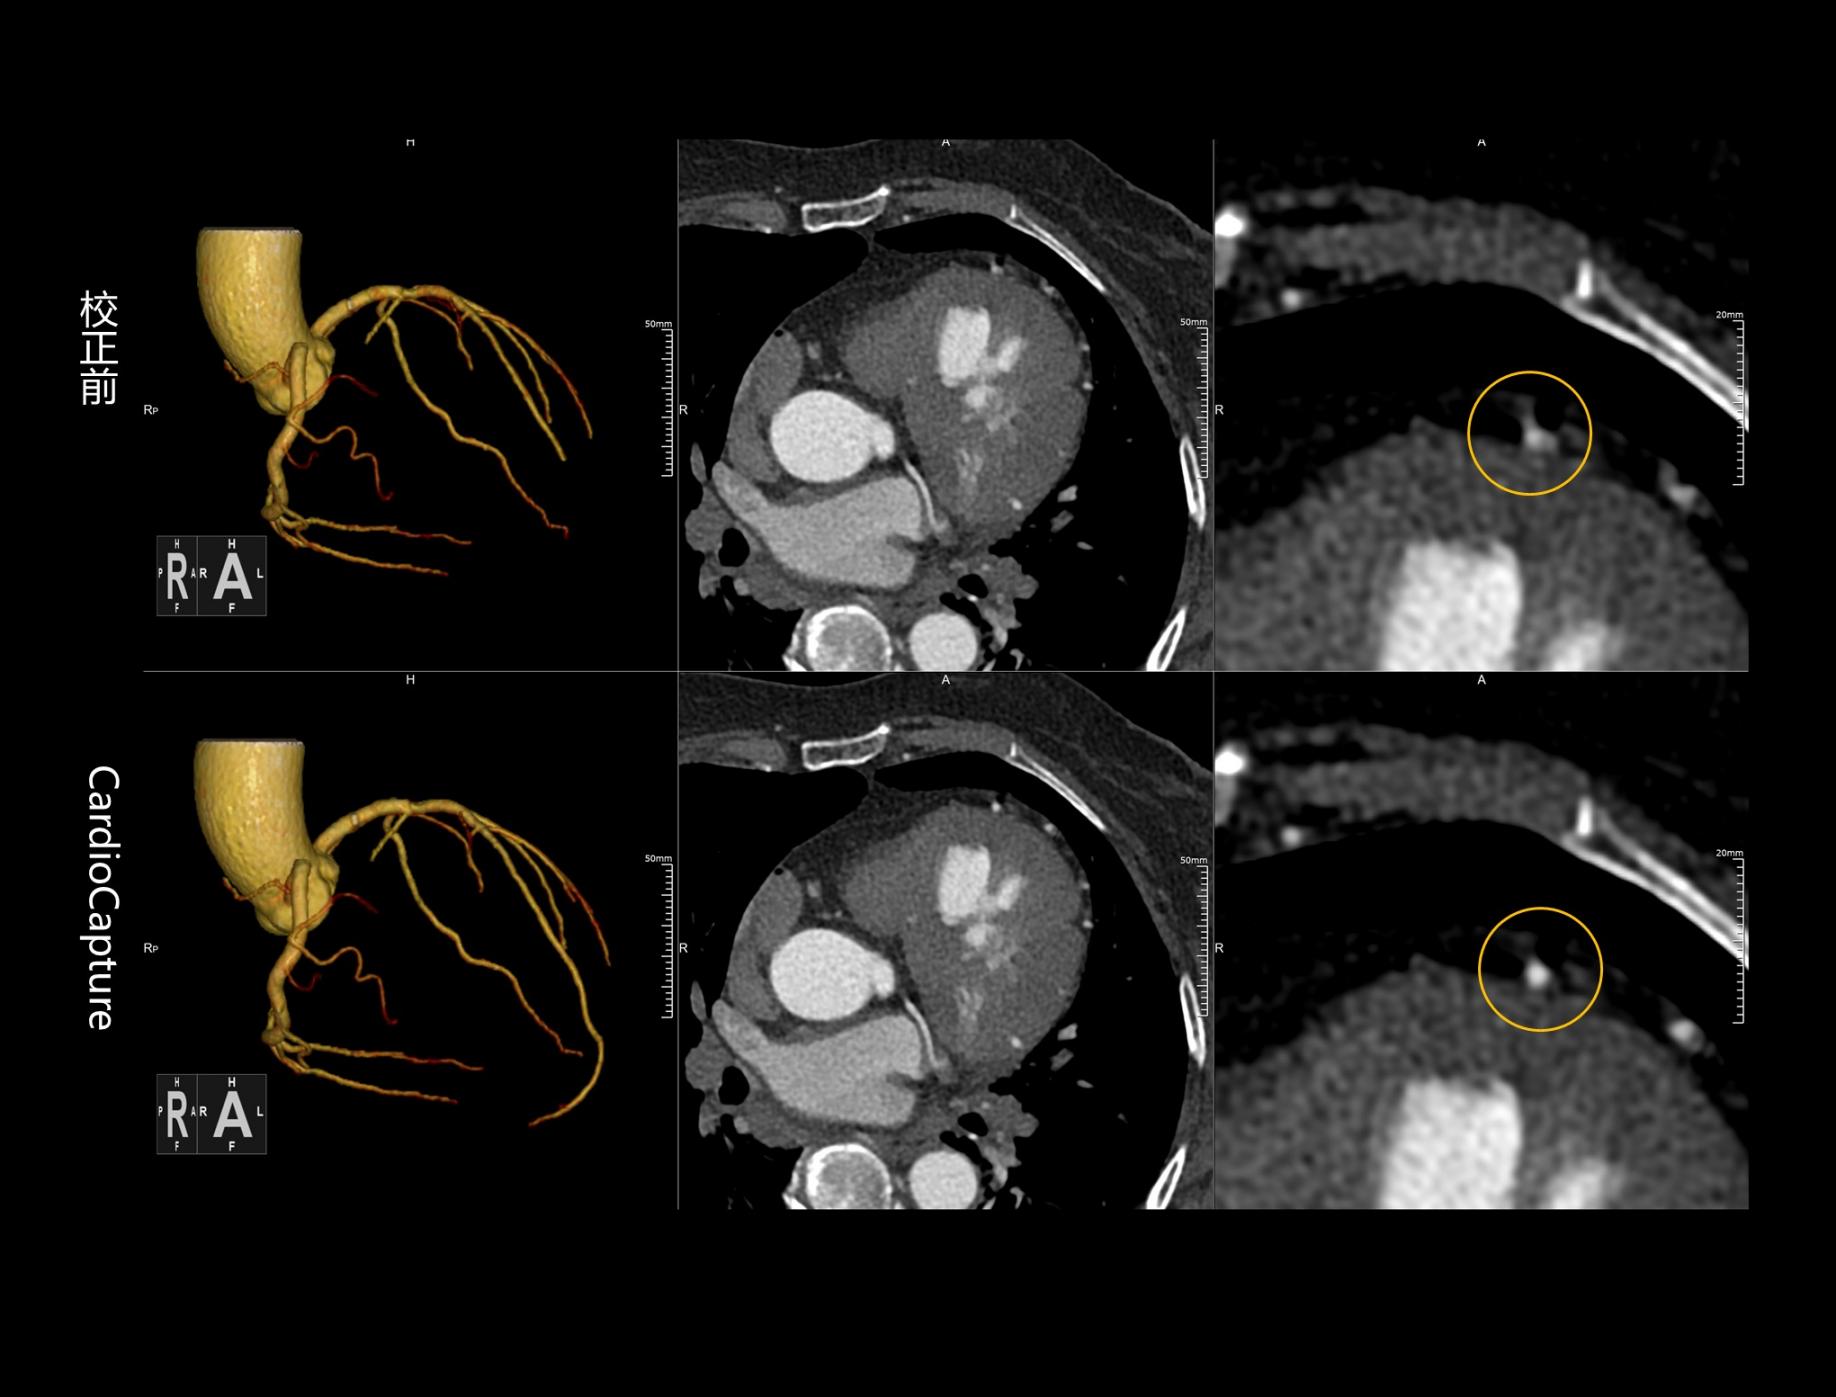

CardioCapture 冠脉追焦技术

CardioCapture AI冠脉追焦技术基于深度学习网络,充分学习各类冠脉图像,以适应不同冠脉场景,精准高效完成冠脉及中心线提取,相较于仅基于CT值和固定解剖模型的传统算法,CardioCapture对于小血管及末端血管显示优势更加显著。

CardioCapture算法采用多时相数据重建,构建更加精细化的冠脉运动向量场,有效提升冠脉运动评估精准度,等效时间分辨率最高可达21毫秒。